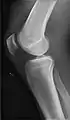

- Knee - AP and Lateral. Intra Condular projections on request

Right knee, anteroposterior

Right knee, lateral